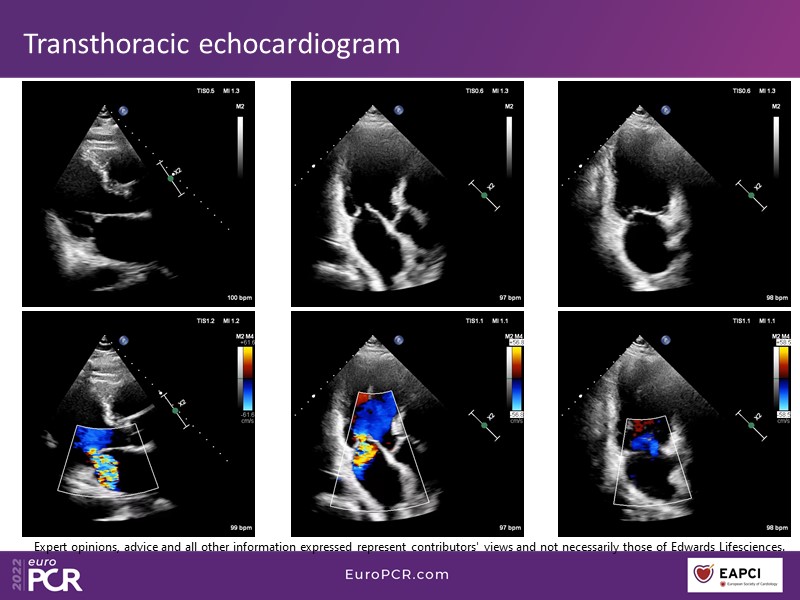

2022: a tipping point in the treatment of mitral regurgitation patients

With study outcomes and clinical cases, this EuroPCR 2022 session will enable you to discuss the anatomical considerations that define suitable candidates for treatment of mitral regurgitation with the PASCAL platform and highlight key differentiators and tips and tricks for its use.

- To discuss which anatomical considerations define suitable candidates for the treatment of mitral regurgitation with the PASCAL platform

- To attend case-based discussions that will highlight key differentiators and tips and tricks when using the PASCAL platform to treat mitral regurgitation